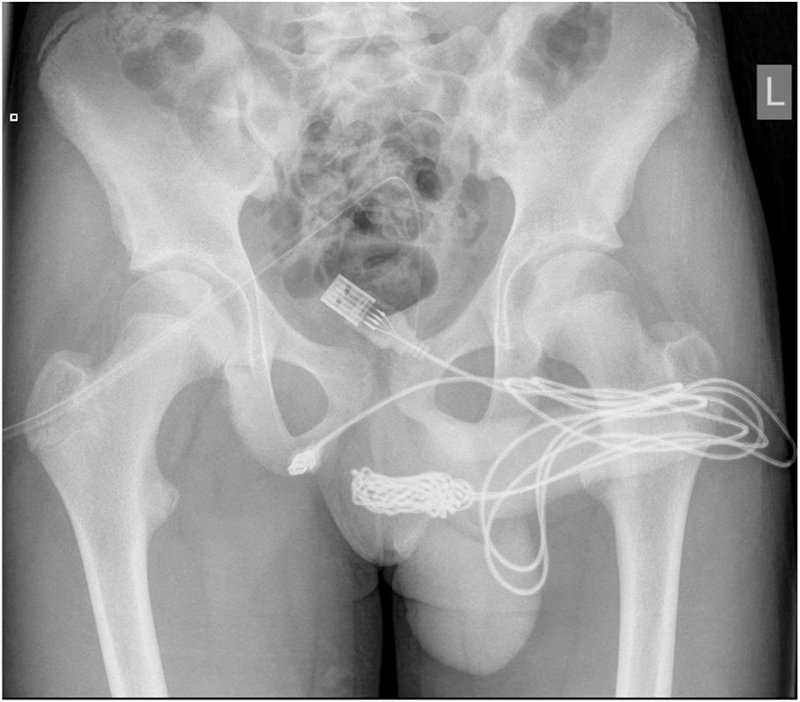

ペニスにUSBケーブルを挿入した少年 抜けなくなって手術で摘出

手術では、球海綿体筋を開き、結び目を取り出して切断。ケーブルの残りは尿道から抜き取られた。

イギリスの15歳の少年が、USBケーブルを「性的好奇心」で尿道に挿入。抜けなくなり、手術によって摘出した。

写真見てもどうしてこうなったか全くわからん

レントゲン怖すぎわろた